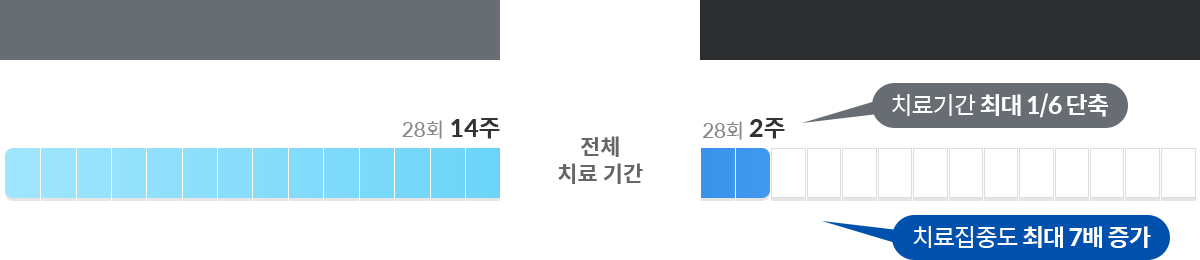

02“2주 간의 집중케어 , 강도 높은 치료로 기간이 단축됩니다”

통 원 치 료

입 원 집 중 치 료

통 원 치 료

입 원 집 중 치 료

주 2회 1~2시간

일상에 지장 없는 스케줄

의료진의 체계적 치료 계획

매일 2회, 주 12~14회 집중치료

24시간 모니터링 후 맞춤치료

주치의 1:1 전담치료

* 치료 횟수와 방법은 환자의 상태와 진단에 따라 달라질 수 있습니다.